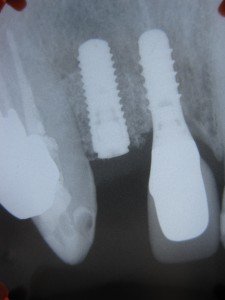

埋入後のレントゲン像です。